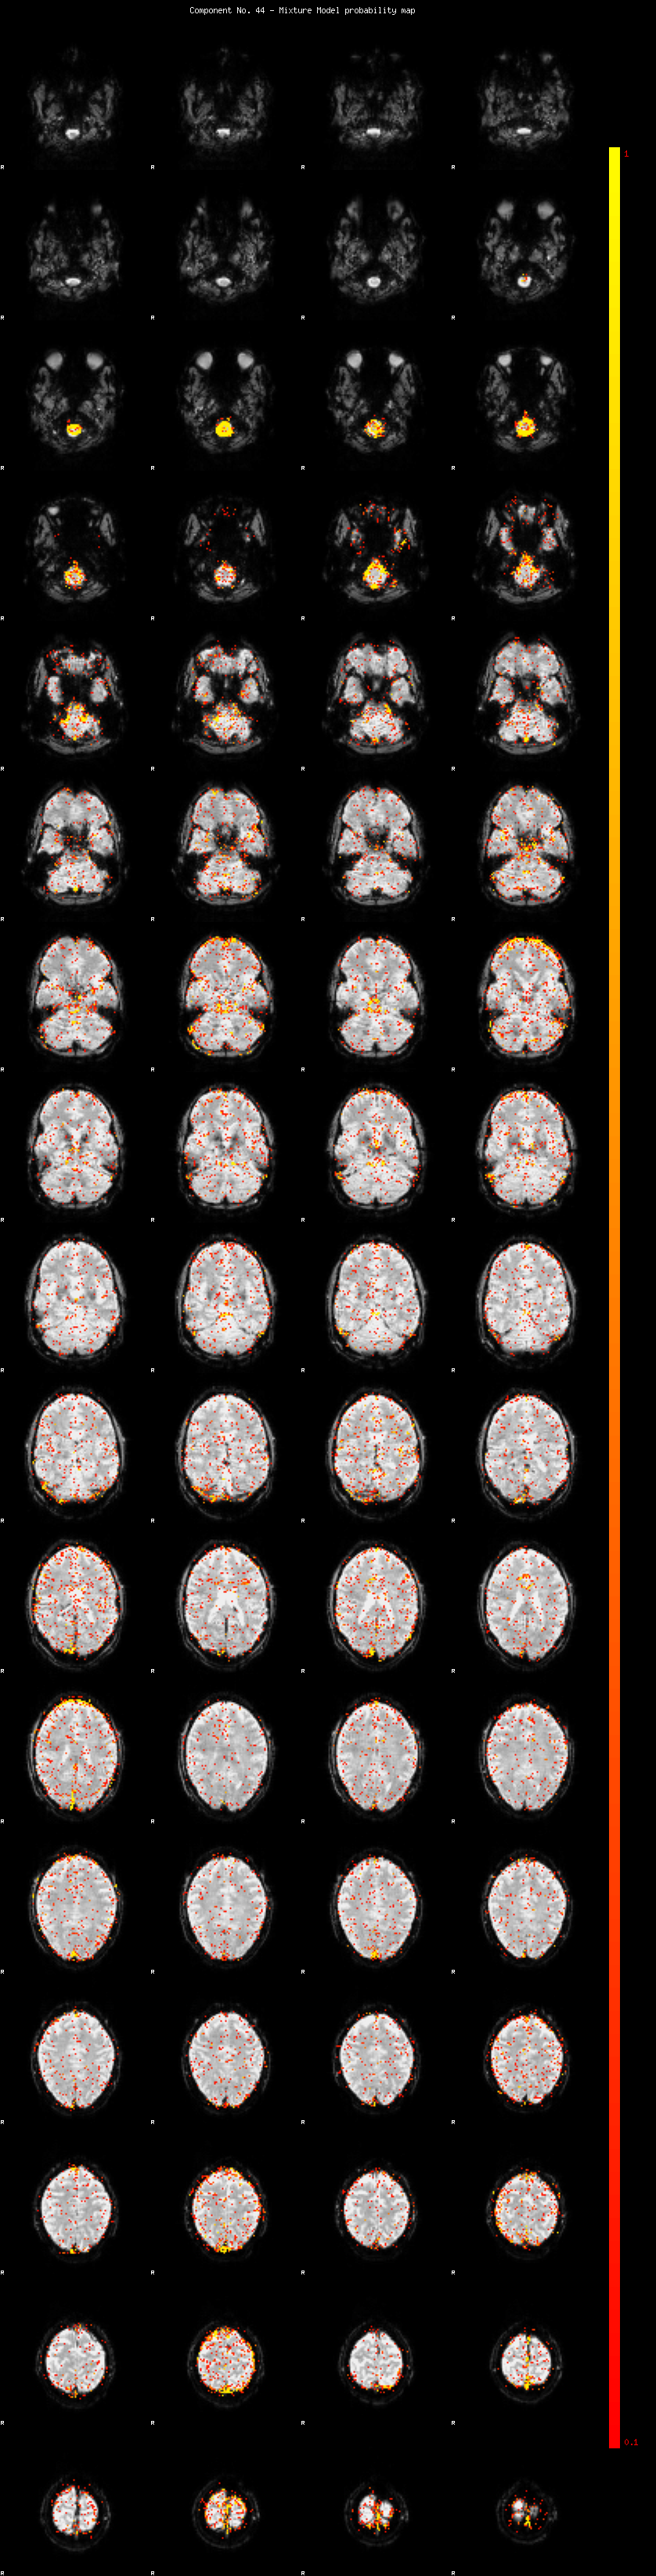

IC_44 Mixture Model fit

Means : -0.000000 2.610789 -2.456160

Vars : 1.000000 2.485155 2.000530

Prop. : 0.950842 0.027361 0.021797